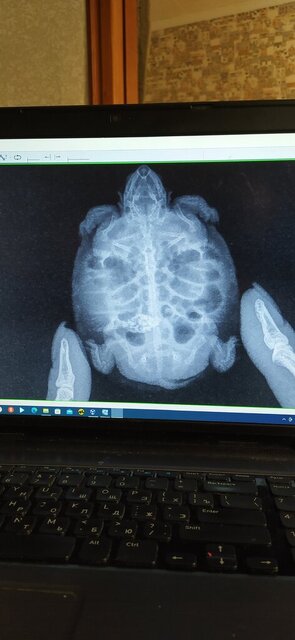

Сделали рентген сверху ,перевернули черепаху и тоже сделали ,какая кто есть кто не знаю ,в общем у меня 2 ренгена ,записали на диск с приложением ,это я с ПК открыл дома .

IMG_20231123_101453.jpg

IMG_20231123_102156.jpg

Мария осмотрела ,и сказала что малыш наелся камней или чего то плотного контрастного ....

@Softik да, это камни : ( видела в канале

но, конечно, у меня большие вопросы к ветеринарам, которые не могут повернуть черепаху лицом и боком к аппарату... это какая-то грустная шутка, потому что не первый раз такое встречаю, что они "не могут" другие проекции